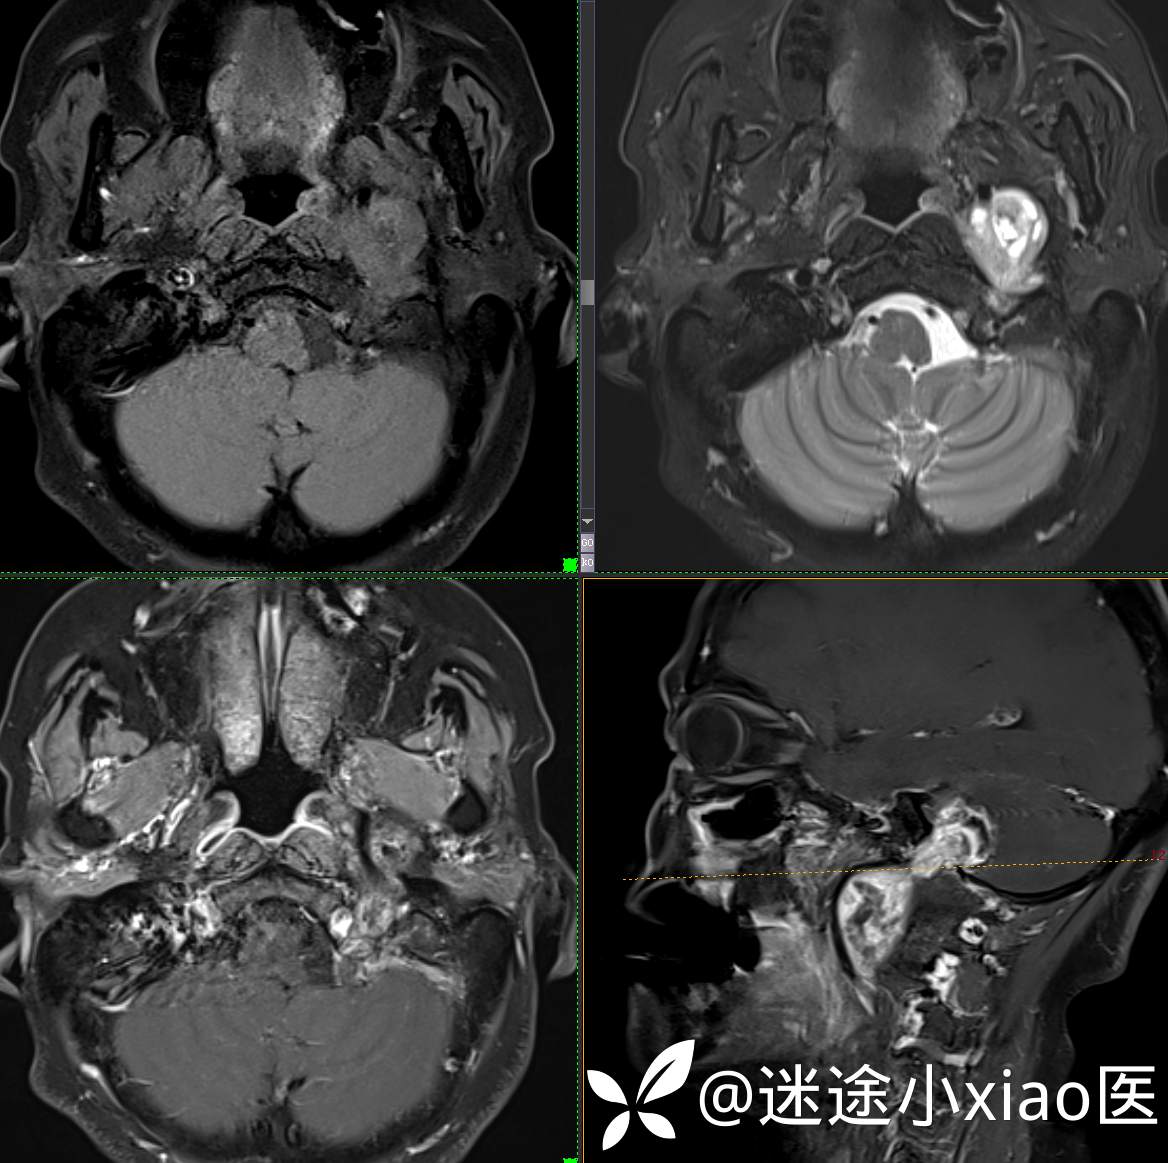

头颈组17:颈静脉孔区占位,副神经节瘤?神经鞘瘤?脑膜瘤?

患者性别:女

患者年龄:57岁

主 诉:  声音嘶哑进食困难伴左侧颌部麻木半年

现病史:  【患者半年前无明显诱因出现声音嘶哑,进食困难,只能进食糊状食物,伴有恶心呕吐,无明显头痛头晕,未加重视。

神经鞘瘤 (117)